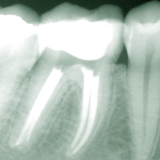

Behandlung PARODONTOLOGIE ENDODONTIE CHIRURGIE IMPLANTOLOGIE PROTHETIK ÄSTHETISCHE ZHK KIEFERORTHOPÄDIE KINDERZAHNHEILK.